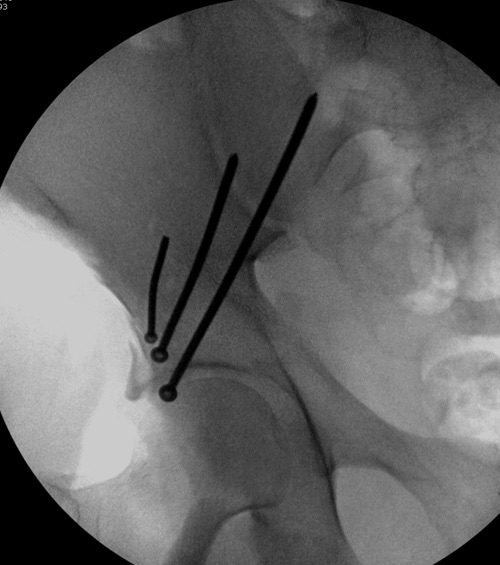

“я и подумал о возможности АВФ. Простите мне мою упрямость”

По поводу лечения, мнения разделились между открытой репозицией или не открывать! Нельзя подгонять метод под имеющийся инвентарь! Предложенный метод идеальный для damage control при разрыве тазового кольца! Метод Илизарова, как спасательный круг, когда кроме спиц ничего, но времена изменились, везде доступны современные методы фиксации! Наружный фиксатор обязывает вести наблюдение за спицами. И еще, вряд ли аппарат со множественными спицами в тазу даст возможность мобилизовать больного! Кроме этого, установка “трансфрактурных спиц” тоже не простая задача, чем винты, открытым методом!

Представленные слайды Александром из Севастополя, имеет ценность, но, кроме inlet, остальные стандартные Judet рентген снимки должны показать правоту принятого решения. Возможно, здесь фиксация перелома вертлужной впадины, но по рентгену трудно понять!

Вместо огромного аппарата, пластина на крыле и винты через AIIS (anterior inferior iliac spine) из места прикрепления прямой мышцы создали бы более элегантную фиксацию. Насчет отсутствия материала, неужели рядом с “Москоу-сити”, в областном центре, где рекламируются передовые платные услуги, отсутствует элементарные пластины и винты? http://bsmp40.ru/services/pay/travma

Фиксация переломов передней колонны намного легче, чем остальных переломов вертлужной впадины. Любой доступ: Smith Petersen, Stoppa или ilio-inguinal. Как фиксировать перелом зависит от желания врача, можно пустить пластину по pelvic brim (linea terminalis) или более щадящее из верхнего окна пластиной, а переднюю колонну длинными межколонными винтами.

Здесь пример перелома передней стенки, где сохранен принцип фиксации передней колонны. Для доступа Smith Petersen с остеотомией ASIS. Мышца сарториус отодвинута, и сделана ре-фиксация на свое место винтами. При хорошем обзоре, наличие Farabeuf или Jungblud forceps облегчит репозицию.